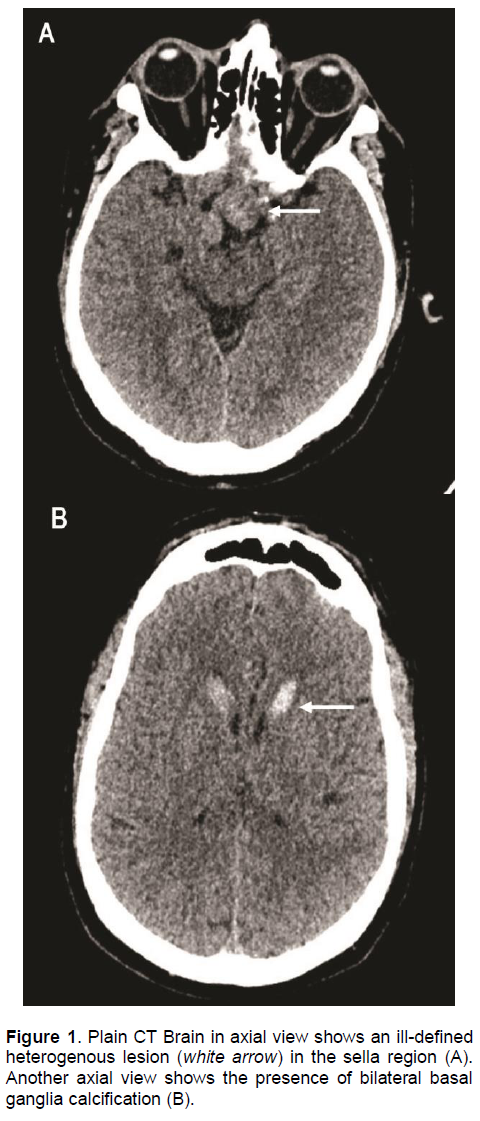

An urgent computed tomography (CT) scan of the brain revealed a suspicious sellar lesion together with bilateral head of caudate nucleus and basal ganglia calcification (Figures 1A and 1B). Magnetic resonance imaging (MRI) of the pituitary demonstrated a heterogeneous sellar mass measuring 2.2 x 1.7 x 3.6 cm extending into the suprasellar cistern displacing the optic chiasm. There was also extension to both cavernous sinuses (right more than left), partly encasing the right internal carotid artery and abuts the left internal carotid artery (Figures 2A and 2B).

Figure 1 . Plain CT Brain in axial view shows an ill-defined heterogenous lesion (white arrow) in the sella region (A). Another axial view shows the presence of bilateral basal ganglia calcification (B).